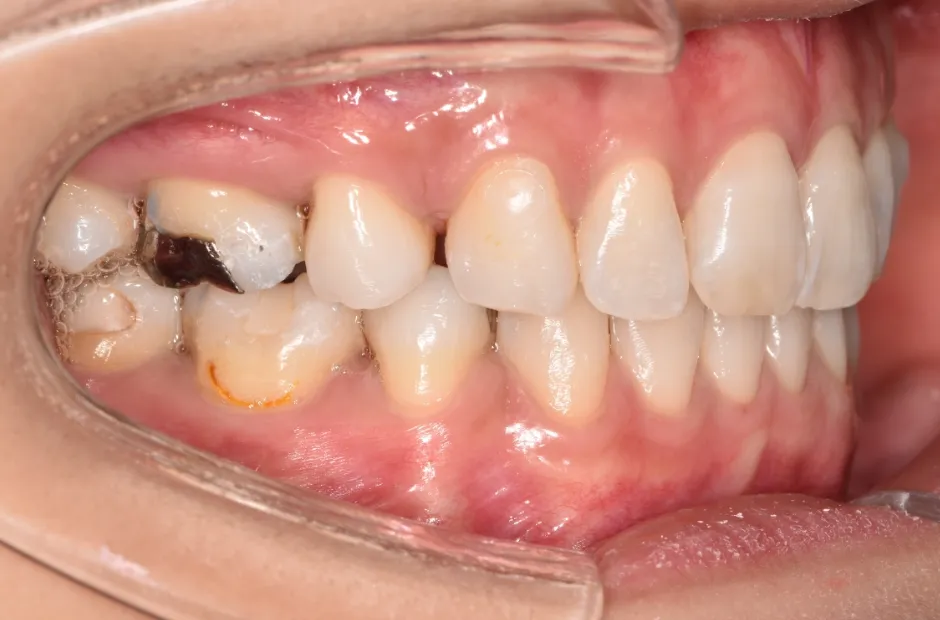

| 診断名・主訴 | 下顎前突、叢生 |

|---|---|

| 年齢・性別 | 23歳・女性 |

| 治療期間・回数 | 3年 |

| 治療に用いた主な装置 | 上顎5,5 下顎4,4 |

| 抜歯部位 | 舌側矯正 |

| 治療費 | 100万円(税抜) |

| リスク・副作用 | 装置による違和感・疼痛・歯肉退縮・歯根吸収・虫歯のリスクなど |

治療前

治療中

治療後